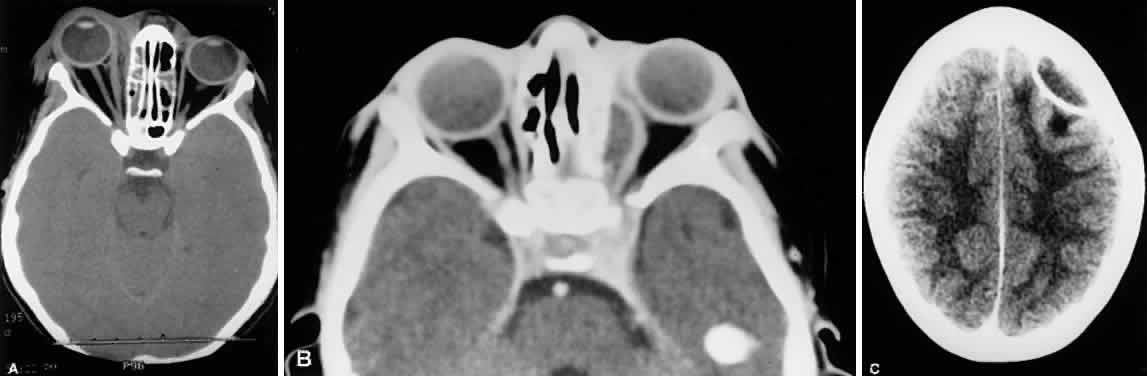

Fig. 22. Inflammatory proptosis originally diagnosed as orbital cellulitis (A), but later diagnosed as necrotic retinoblastoma (B).

Fig. 23. Inflammatory proptosis originally diagnosed as orbital cellulitis, but later diagnosed as rhabdomyosarcoma. Figure depicts patient's status after biopsy through brow.

Fig. 24. A. Phlegmon of the medial orbit due to ethmoid sinusitis. There is no distinct abscess cavity. Note swelling and displacement of the medial rectus muscle. B. Subperiosteal abscess. C. Intracranial abscess secondary to ethmoid sinusitis with orbital cellulitis.